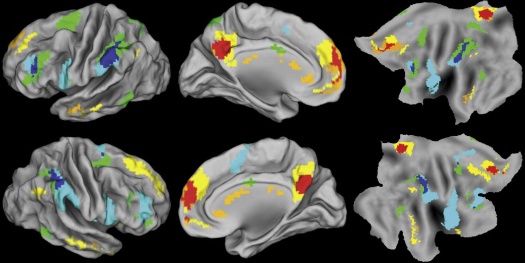

A new study published in NeuroImage found that separate neural pathways are used alternately for empathetic and analytic problem solving. The study compares it to a see-saw. When you’re busy empathizing, the neural network for analysis is repressed, and this switches according to the task at hand.

Anthony Jack, an assistant professor in cognitive science at Case Western Reserve University and lead author of the study, relates the idea to an optical illusion. You can see a duck or a rabbit in the image, but not both at the same time. This limitation to what you can see is called perceptual rivalry. Jack’s new study takes this concept beyond visual perception, and investigates how the brain processes situations. It found separate neural networks for social/emotional processing and for logical analysis.

The study took magnetic resonance images of 45 college students as they were presented with problems involving social issues or physics. The MRIs showed that separate regions of the brain activated and deactivated according to the type of problem.